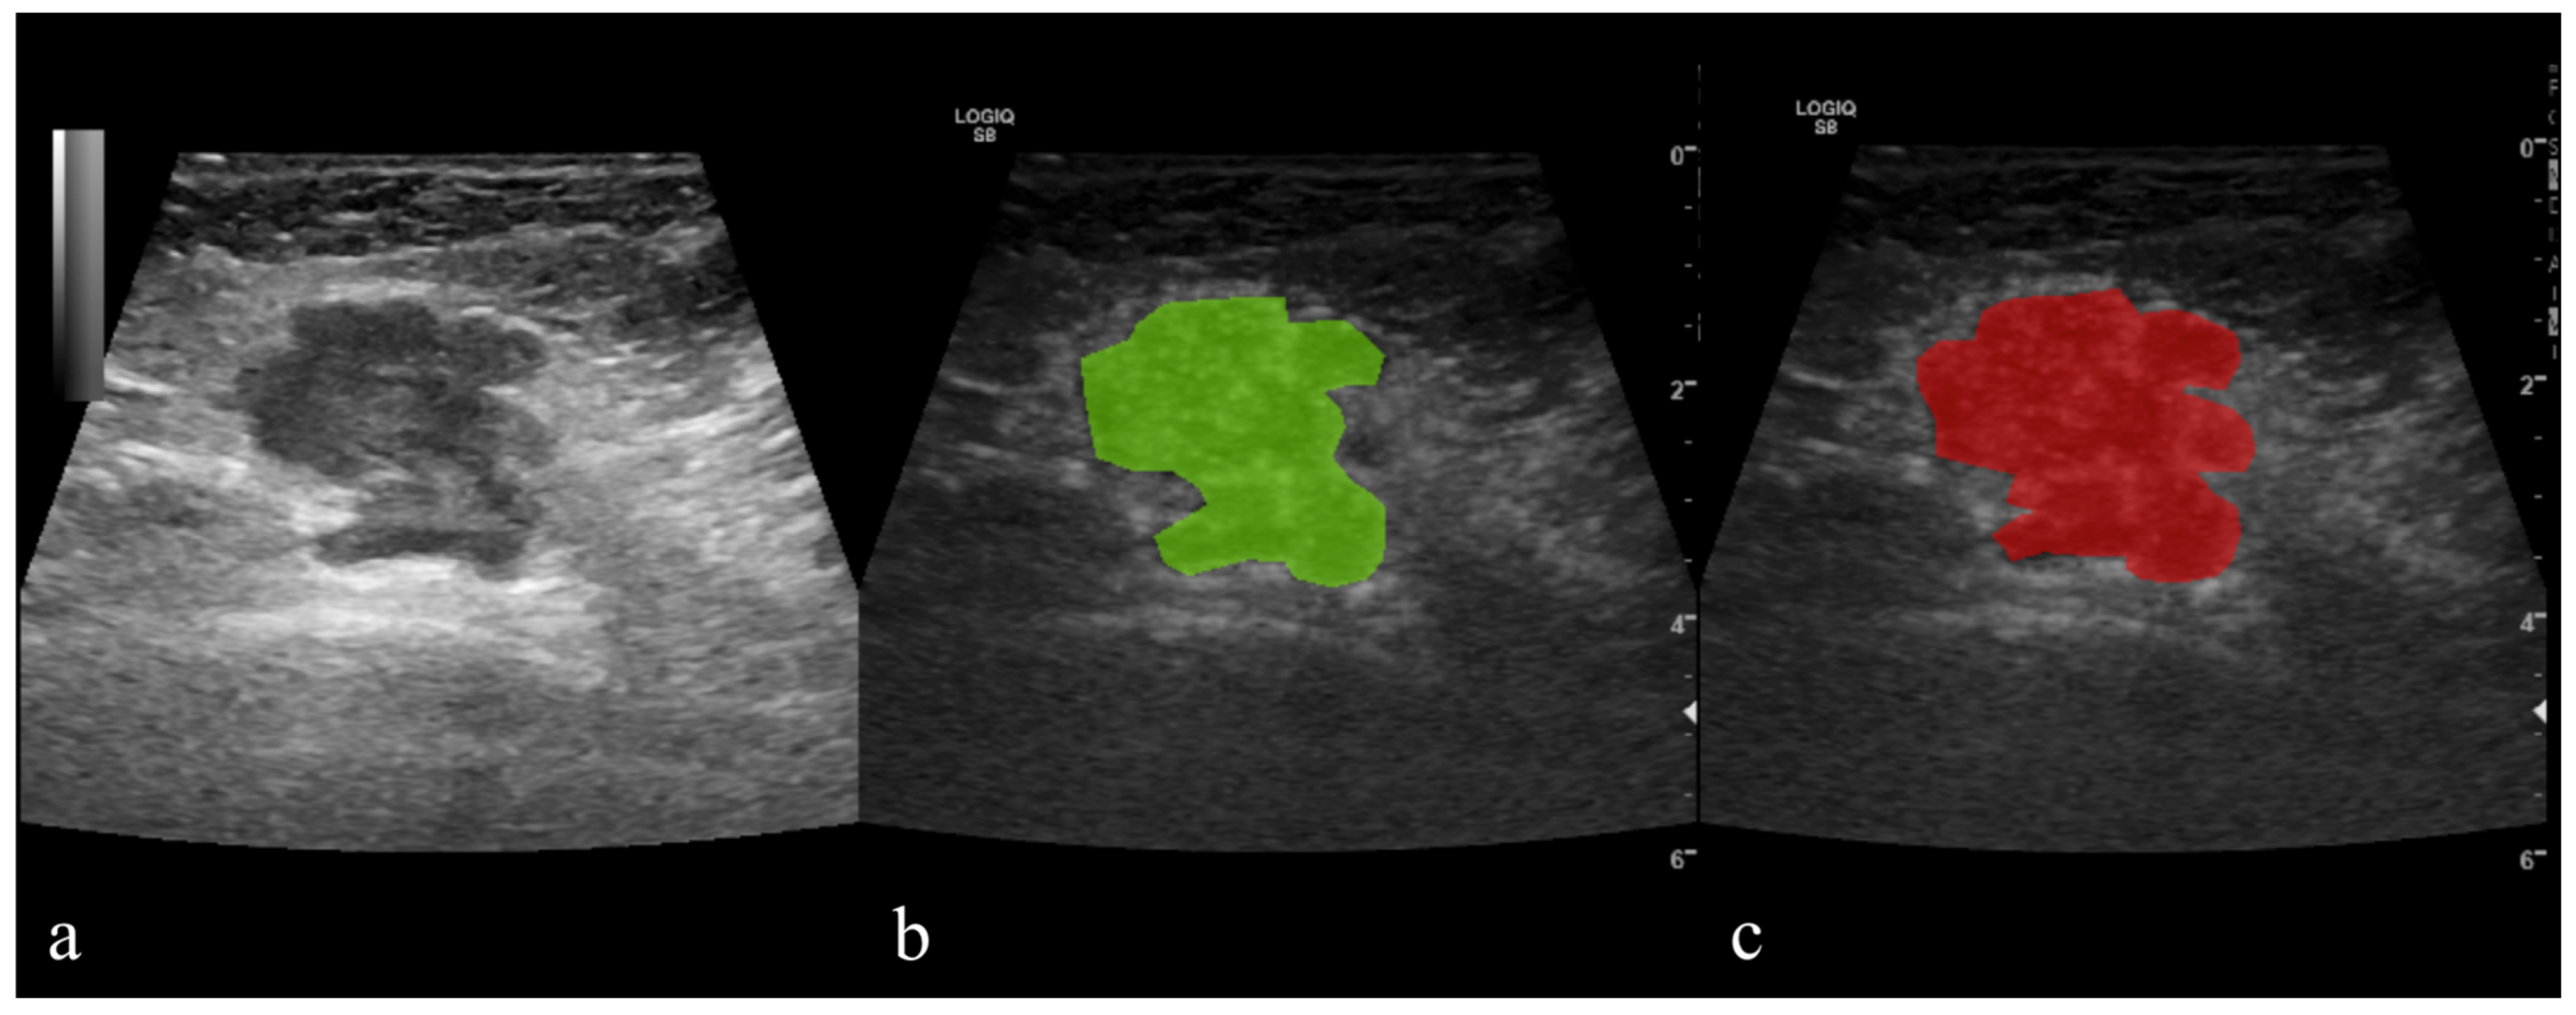

A semi-automatic level-set technique was used for the definition and positioning of ROI using gradient and geometry coordinates. As this technique does not require the manual delineation of the structure of interest contours, the inter- and intra-observer reproducibility was not assessed in this study. The researcher placed a seed in the area of interest, and the software automatically delineated the area based on gradient and geometrical contours. When necessary, manual corrections were applied (Figure 2). Before the extraction of texture parameters, the imported image’s grey levels were normalized based on the mean and three standard deviations of grey level intensities to reduce the contrast and brightness variations (which could affect the true image textures). The parameters are detailed in the table below (Table 1).

Figure 2.

Contrast-enhanced ultrasound (CEUS) of histologically proven breast cancer; (a) grayscale image; (b,c) hybrid images with the tumor applied regions of interest (ROIs) that were automatically delineated by the software (green) and the final ROI after manual correction (red).